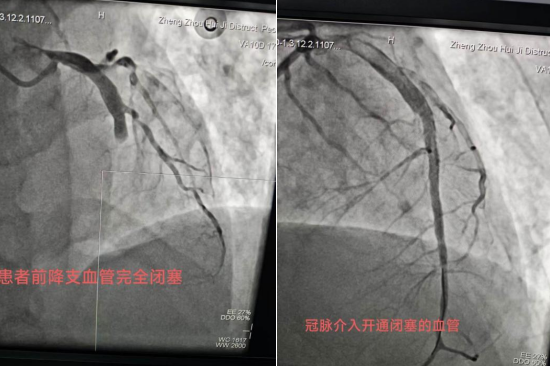

生命通道:院前呼叫院内开通绿色通道,启动胸痛中心,胸痛二线会诊,救护车在凌晨寂静的街道上呼啸而过,01时30分抵达惠济区人民医院急诊科。患者到达医院后与院内无缝衔接,胸痛中心已提前启动导管室准备,心内科介入团队与急救团队完成"零时差"交接。血管造影显示前降支近端完全闭塞,成功植入支架开通血管,患者血压回升至120/78mmHg,ST段回落至基线水平。